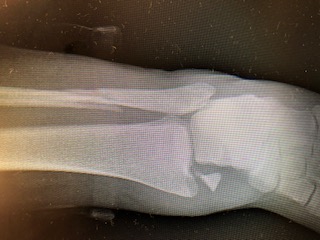

On June 2, 2019, I went to my friend's house with my skateboard in my hand. We had skated a while and were on our way back to her house when I hit an uneven portion of the sidewalk and fell. I immediately knew I had broken my ankle. Off the the emergency room where they took x-rays and set my leg in a soft cast. The nurse told my parents that we should make an appointment with an orthopedic surgeon because I would need surgery. We went to the orthopedist they recommended - and although he was nice and explained what the surgery would be like, my parents felt like the whole experience of being in that office was disappointing. There were dozens of people waiting for over an hour to see the doctor. My mom said it felt like we were all just a herd of cattle - being shuffled from one waiting area to another. We went home and my mom did some extensive research. She found Dr. Behrens and Hospital for Special Surgery. She was very impressed with Dr. Behrens extensive education, qualifications, research and reviews from other patients. We made the appointment and had a consultation. Dr. Behrens office was nothing like the one we'd been to. The staff was extremely professional and informative. We waited no more than 20 minutes from the time we arrived to when we saw the doctor. He was very thorough in his explanation of what I did and how he was going to fix it. He made me feel very comfortable. The day of my surgery arrived and the staff at NY Presbyterian were wonderful. They explained every step of my procedure and made sure I didn't have any questions. They kept my parents informed every step of the way. I followed Dr. Behrens instructions to remain off my feet for the next 4 weeks and then we returned for a check up. The took another x-ray and everything looked great. I was now allowed to walk in the boot I'd been in. A few weeks later I went back again - my ankle looked fantastic. Now I could walk in a soft brace. I just went back for my last visit. My ankle has healed beautifully and I have no restrictions. I may not play sports - but I am back in the game of traveling to Manhattan every day to go to school, participating in gym, and leading the same active lifestyle I had before. I thank Dr. Behrens and his staff for making me whole again!